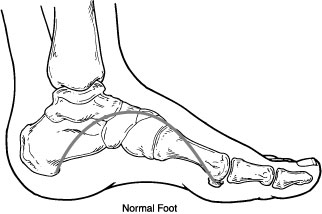

Motor nerves control muscles and give them their strength and tone. Peripheral neuropathy may also cause muscle weakness and loss of reflexes, especially at the ankle, leading to changes in the way a person walks. Foot deformities, such as bunions and hammertoes, may occur, as well as collapse of the midfoot, a condition known as Charcot foot.

In Charcot foot, the joints in the foot collapse and the foot eventually becomes deformed

The loss of foot structure may also cause shoes to rub against toes, causing sores. Blisters and sores may appear on numb areas of the foot because an injury goes unnoticed. If an infection occurs and is not treated promptly, the infection may spread to the bone, a condition known as osteomyelitis, and the foot may have to be amputated. Many amputations are preventable if minor problems are caught and treated in time.